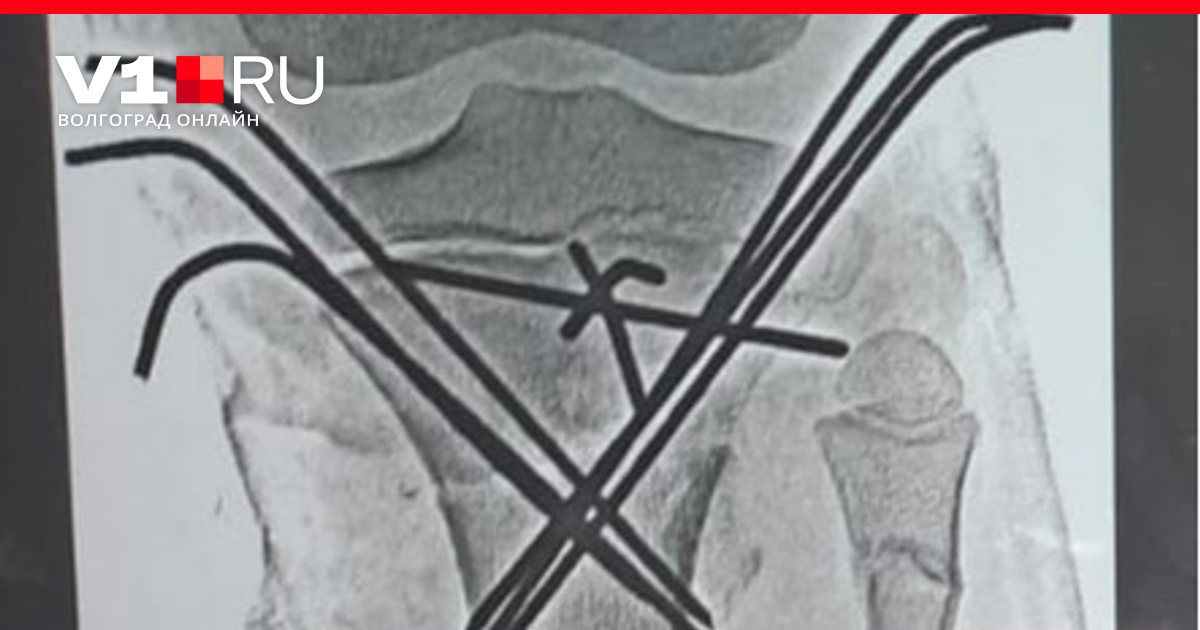

— Врачи диагностировали у него сочетанную автодорожную травму и травматический шок второй степени, — сообщили в комитете здравоохранения Волгоградской области. — У мотоциклиста было 23 перелома: закрытая черепно-мозговая травма, перелом ключицы, костей таза со смещением, перелом позвоночника, ушиб легких и другие.

Травматологам пришлось провести четыре этапа хирургических вмешательств.

— Сейчас пациент продолжает лечение в детском ортопедо-травматологическом отделении больницы № 7, где ему предстоит еще ряд операций по удалению скрепляющих металлических конструкций, которые находятся в конечностях, — добавили в облздраве. — Медики делают всё возможное, чтобы поставить парнишку на ноги. Необычным пациентом занимаются лучшие специалисты волгоградского региона.